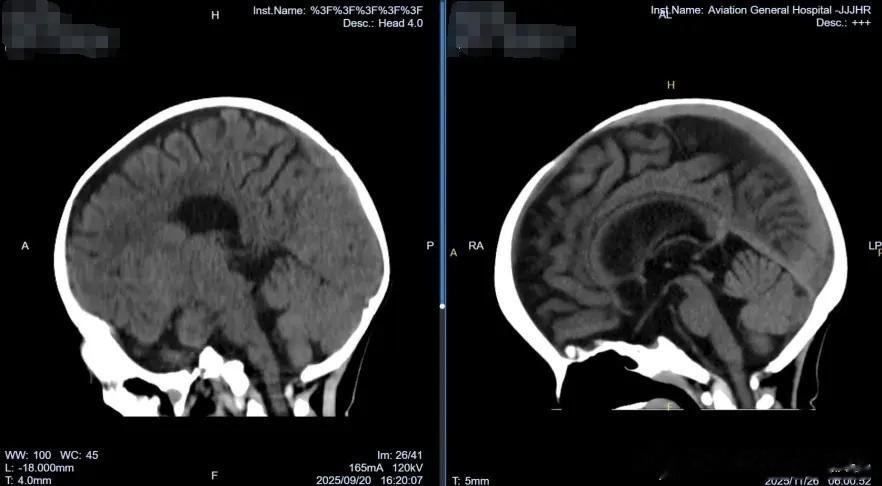

通过放置在腹壁外的引流管,医疗团队每天监测引流情况,并逐步调整引流瓶高度,促进大脑自然复位。这一外引流设计避免了在感染风险期植入永久性分流装置。经过近两个月的恢复,2025年11月底,瑶瑶再次接受手术,移除了硬膜下-腹腔分流管。次日复查头颅CT显示:双侧硬膜下仅残留少量低密度影,脑组织复位良好,中线结构居中。